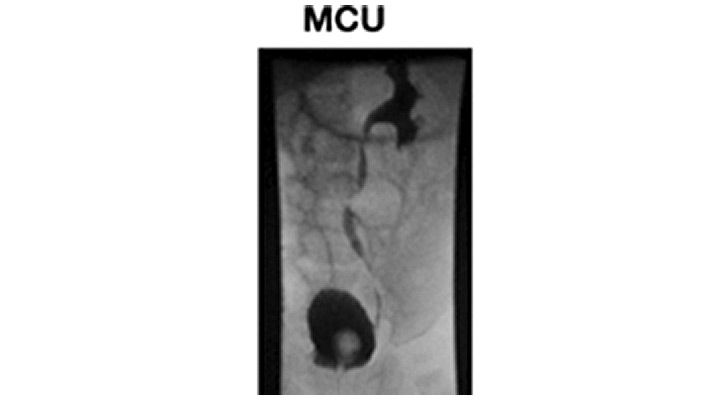

Bei dieser Untersuchung wird dem Kind über die Harnröhre ein Blasenkatheter in die Blase eingelegt, um in diese langsam Kontrastmittel einzufüllen. Wenn das Kind anschließend Wasser lässt, kann mit einer Röntgenvorrichtung sowohl die Blasengröße bestimmt, als auch einen Rückfluss von Kontrastmittel aus der Blase in Richtung Nieren diagnostiziert und darüber hinaus die Harnröhrenkonfiguration beurteilt werden.